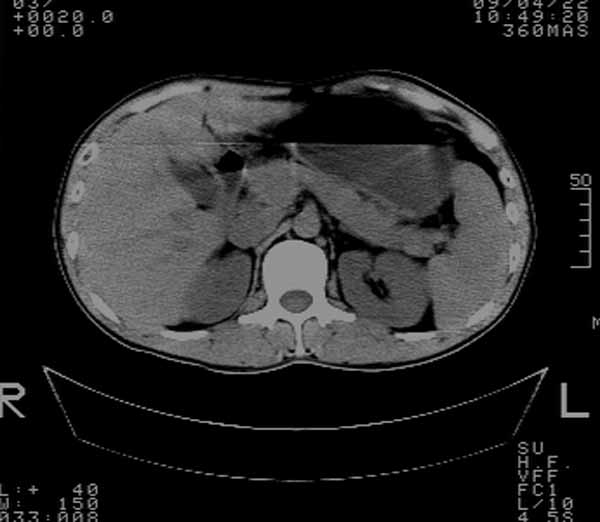

标题: CT19521:肝占位

m,37y,右胁部疼痛一周,无其它不适.血分析正常,未作其他检查.不愿做增强.

有晕征 考虑肝脓肿 胆囊炎

1,肝占位,(病灶有假包膜,内见液化坏死)考虑肝癌可能大。

2,胸水

假包膜征,中心坏死,肝癌百分百